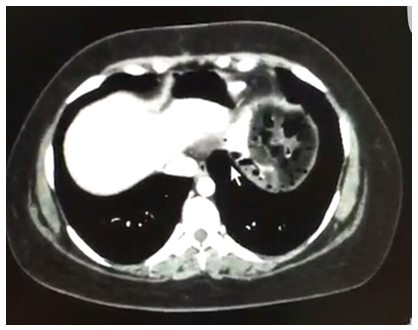

J.N.M.P., 33 years old, female, was submitted to a laparoscopic Roux-in-Y Gastric Bypass due to severe obesity (BMI 41 kg/m2) and hepatic steatosis. On the seventh postoperative day (PO), she complained of bilateral shoulder pain. There were no significant alterations on the physical examination, no fever and normal pulse. The secretion present in the drain was serous and methylene blue oral intake test was negative. Laboratory tests revealed leukocytosis of 13,000 without other changes. Abdominal CT scan with oral and intravenous contrast showed no signs of leakage, free intracavitary fluids or collections but the presence of a large volume pneumoperitoneum, not expected for a seventh postoperative day. Leading with a hypothetical fistula, consistent with the indirect CT findings, and in the absence of sepsis signs, we started a treatment with fasting, antibiotic therapy and parenteral nutrition. Three days later, there was 80 to 90% improvement of the clinical onset of shoulder pain, and reduction of leukocytosis. Eight days later, another CT showed an important reduction in the pneumoperitoneum volume, which allowed to reestablish oral intake. The patient had a good evolution. Another Tomography, fifteen days after hospital discharge, showed no pneumoperitoneum (Figures 1-4).1–3

Figure 1 TC ABDOME 01.